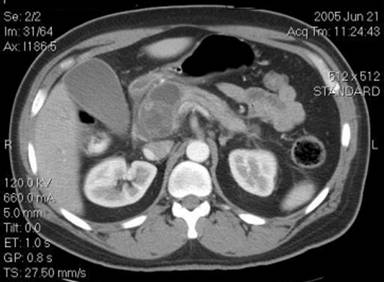

Two weeks after the initiation of azathioprine, he was admitted with severe abdominal pain, nausea and vomiting and elevated amylase and lipase. The pancreatic pseudocyst of the head of the pancreas was increased in size (4.0x3.9 cm), the remainder of the hypodense lesions of the pancreas were also slightly larger in size. A diagnosis of azathioprine-induced pancreatitis was made, as exploration for other causes of worsening was negative. He had a EUS evaluation to rule out other causes including intraductal papillary mucinous neoplasm. He had no history of alcohol abuse or cigarette smoking. There was no evidence of choledocholithiasis and evaluation of the medication list for any cause of pancreatitis other than azathioprine was negative. Azathioprine was stopped and mycophenolate mofetil was started for autoimmune hepatitis and autoimmune pancreatitis. Repeat CT after 4 weeks for persistent abdominal pain, nausea and vomiting showed extrinsic compression of the duodenum by the pseudocyst (Figure 1). ERCP with cyst duodenostomy was performed at that time with subsequent improvement of symptoms and biochemical improvement.

Figure 1. CT abdomen showing pseudocyst in the head of the pancreas compressing the common bile duct and duodenum. |